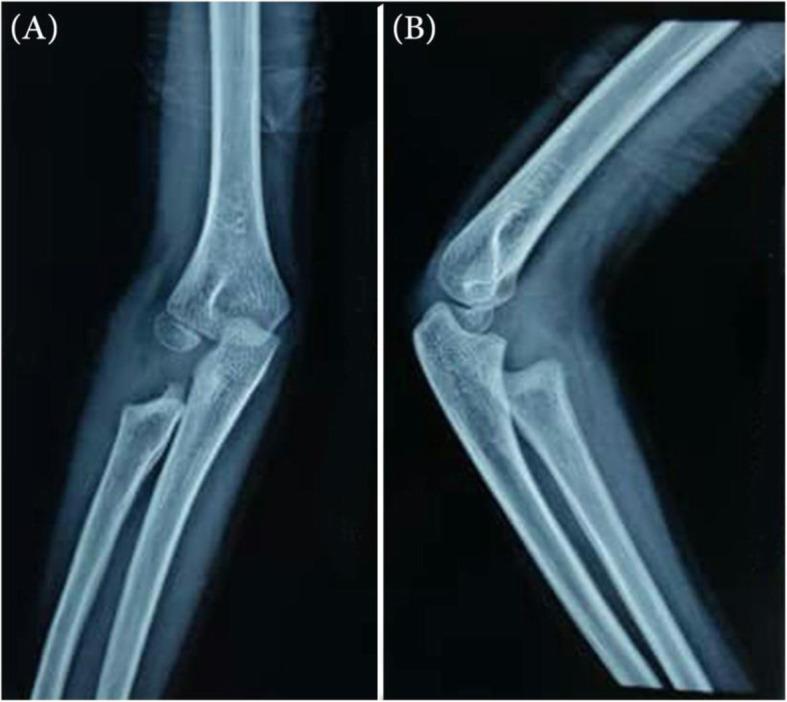

In this study, we report a case of DEH located in the radial head of the right elbow of a 10-year-old boy, which was presented with elbow pain and limited range of motion. In clinical examination, an asymmetrical enlargement was observed over the elbow. The lesion was resected surgically, and the patient's symptoms resolved afterward. The histologic analysis of the lesion confirmed the diagnosis of DEH.

本研究报告了一例 10 岁男孩右侧肘关节桡骨小头 DEH,表现为肘部疼痛和活动范围受限。临床检查发现肘部有不对称性增大。病变通过手术切除,患者症状随后得到缓解。病变的组织学分析证实了 DEH 的诊断。